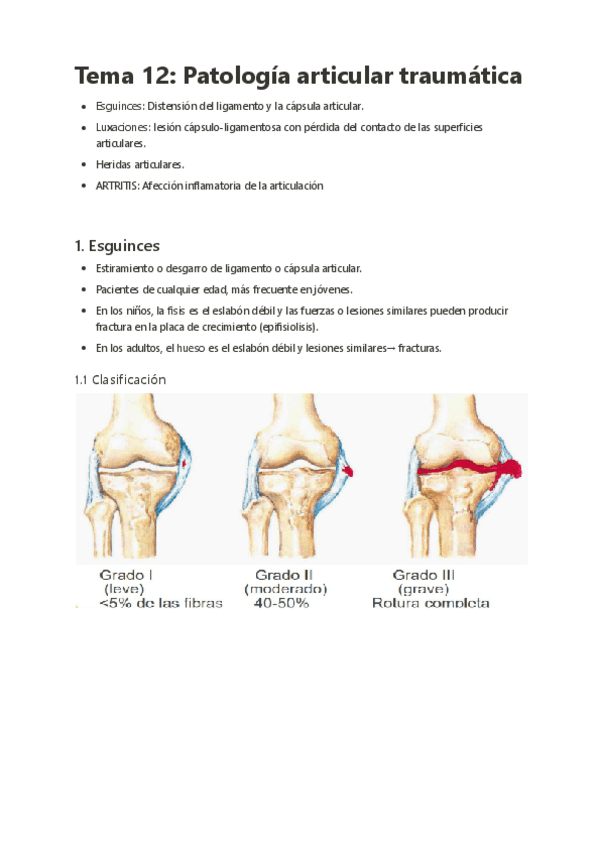

He publicado nuevos apuntes de 2º Afecciones médico-quirúrgicas I: Tema-12-Patologia-articular-traumatica.pdf